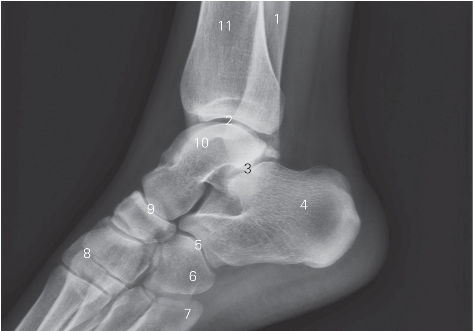

图7-8 踝关节侧位DR平片

1 腓骨 fibula 2 踝关节 ankle joint

3 距跟关节 talocalcaneal joint 4 跟骨 calcaneus

5 跟骰关节 calcaneocuboid joint 6 骰骨 cuboid

7 第5跖骨 fifth matatarsal bone

8 跗跖关节 tarsometatarsal joint

9 距舟关节 talonavicular joint

10 距骨 talus 11 胫骨 tibia